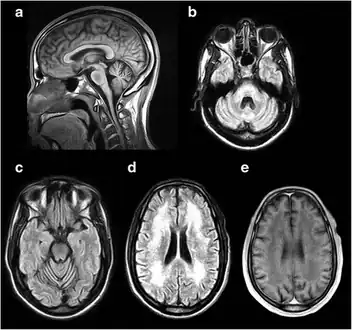

a-e) MRI of the brain demonstrating characteristic findings in DRPLA

a-e) MRI of the brain demonstrating characteristic findings in DRPLA Optic atrophy on fundoscopic exam in DRPLA. Very pale optic discs are evident bilaterally. a) OS, and b) OD

To quantify the extent of the disease, an MRI, EEG and neuropsychological testing are recommended. Seizures are treated with anticonvulsants and psychiatric disturbances with psychotropic medications. Physical therapy has also been recommended to maintain function as the condition progresses and occupational therapy to focus on activities of daily living, advice for carers and adaptation to the environment.